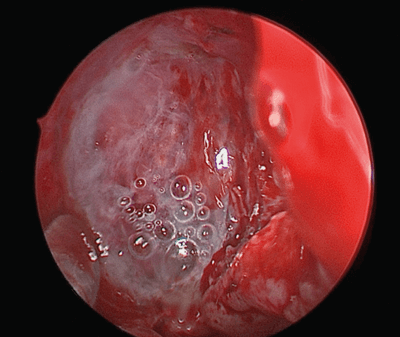

Once the common cavity has been created, any meningoencephalocele at the skull base defect is either excised or contracted using bipolar diathermy (see Figure 2). The surrounding mucosa at the defect is removed to freshen the edge by approximately 5mm, as previously described by Wormald.

Figure 2. Fluorescein stained meningocele.